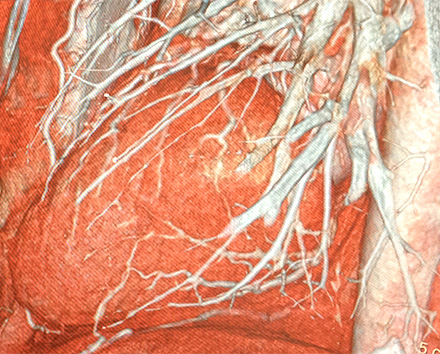

STL変換されたデータを基に、適切な3Dプリンタを用いて状況に応じた実寸モデルの作成を行います。

撮影データを基に構成するので、微細な構造や質感を再現でき従来以上の造形物を提供する事が可能になります。